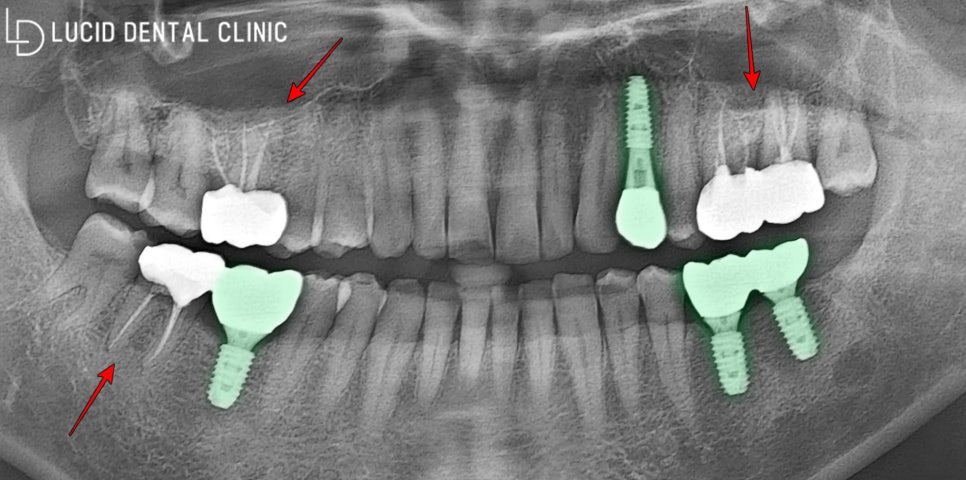

- 치료 종료

사진과 같이 신경치료와 임플란트 수술 로

한층 높아진 심미와 기능을 되찾아드렸습니다.